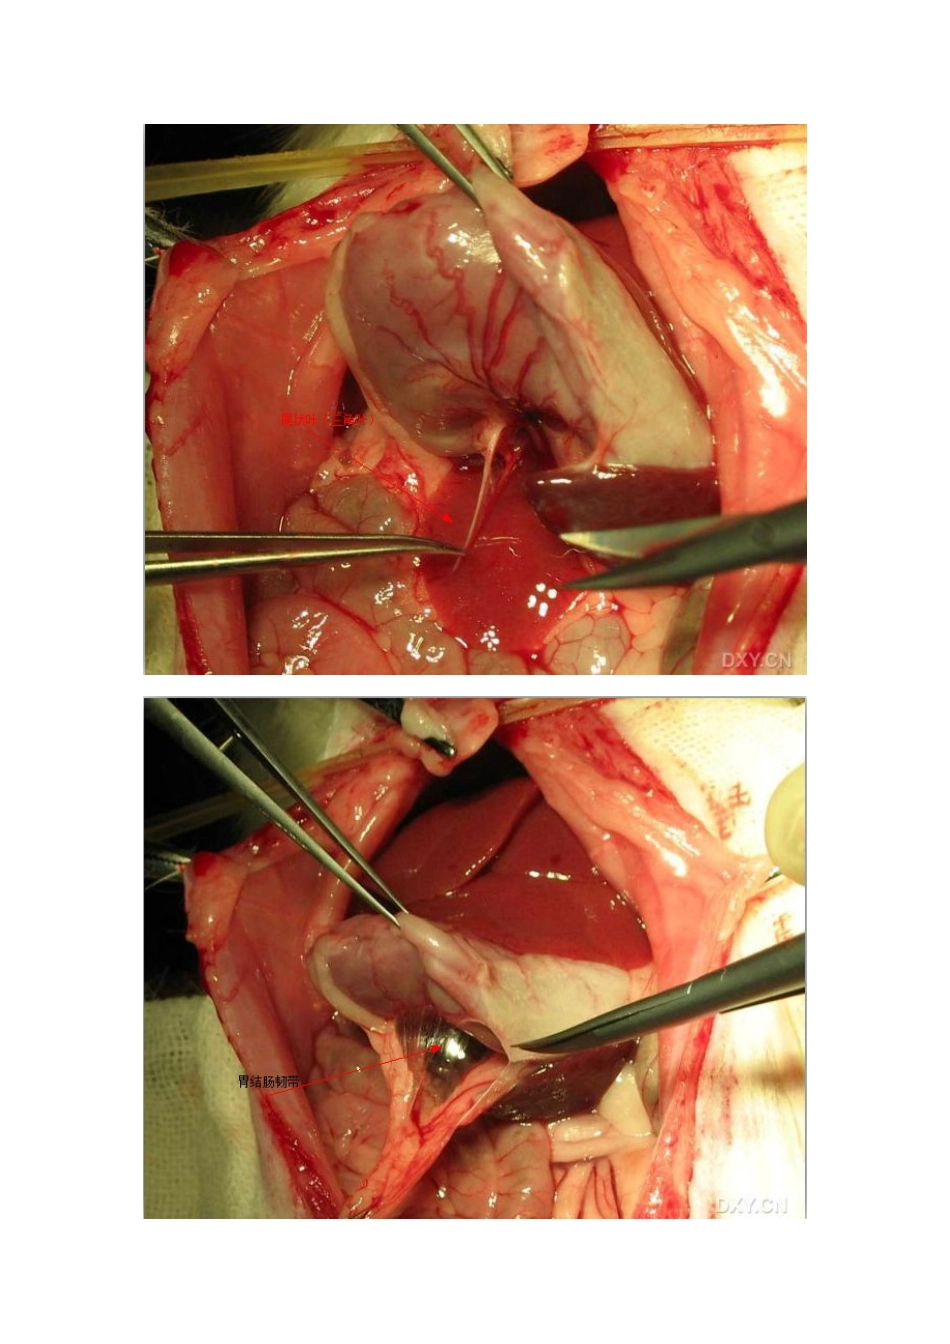

大鼠肝脏图解

大鼠肝脏解剖图解